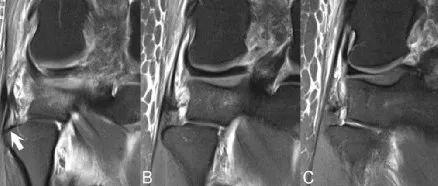

在MCL损伤的MRI表现中,I级损伤表现为韧带基本正常,但有韧带周围水肿。II级损伤则表现为部分增厚、部分破裂,以及比I级更明显的水肿和/或出血。III级损伤则有明显的韧带断裂。急性孤立的MCL断裂可能与股骨外侧髁、胫骨外侧平台或两者同时的骨挫伤类型相关。慢性MCL损伤可能会暴露出丝状肌腱,这是由于损伤时的伸展和轻微拉长状态下的愈合所致。